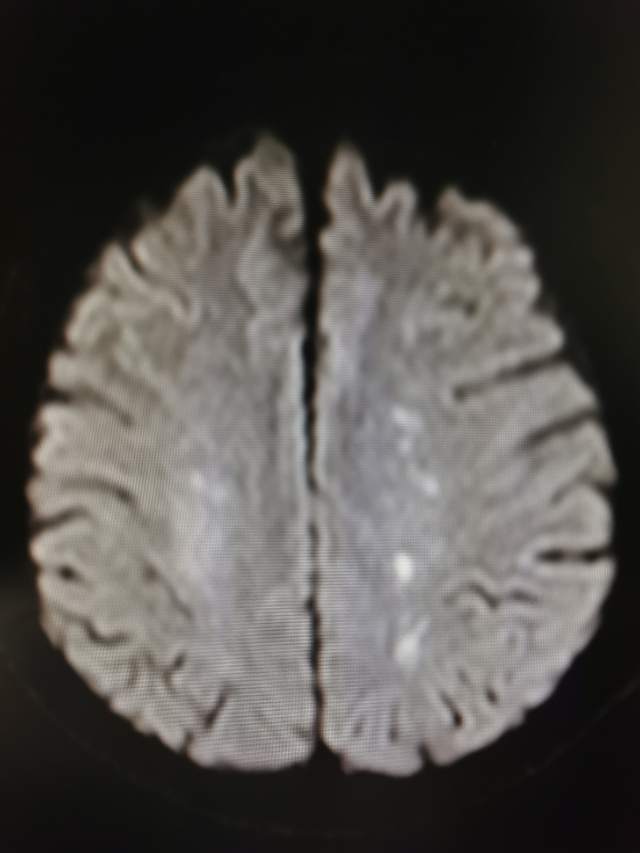

49岁中年帅哥,近期出现记忆力减退和走路肢体无力17天。既往有糖尿病病史17年,控制差。

头颅MRI提示:左侧分水岭区点状脑梗塞,右侧半卵圆区脑梗塞

左侧散在的多发点状脑梗塞与左侧颈动脉蹼相关,属于症状性蹼,长期口服抗血小板药物无效。